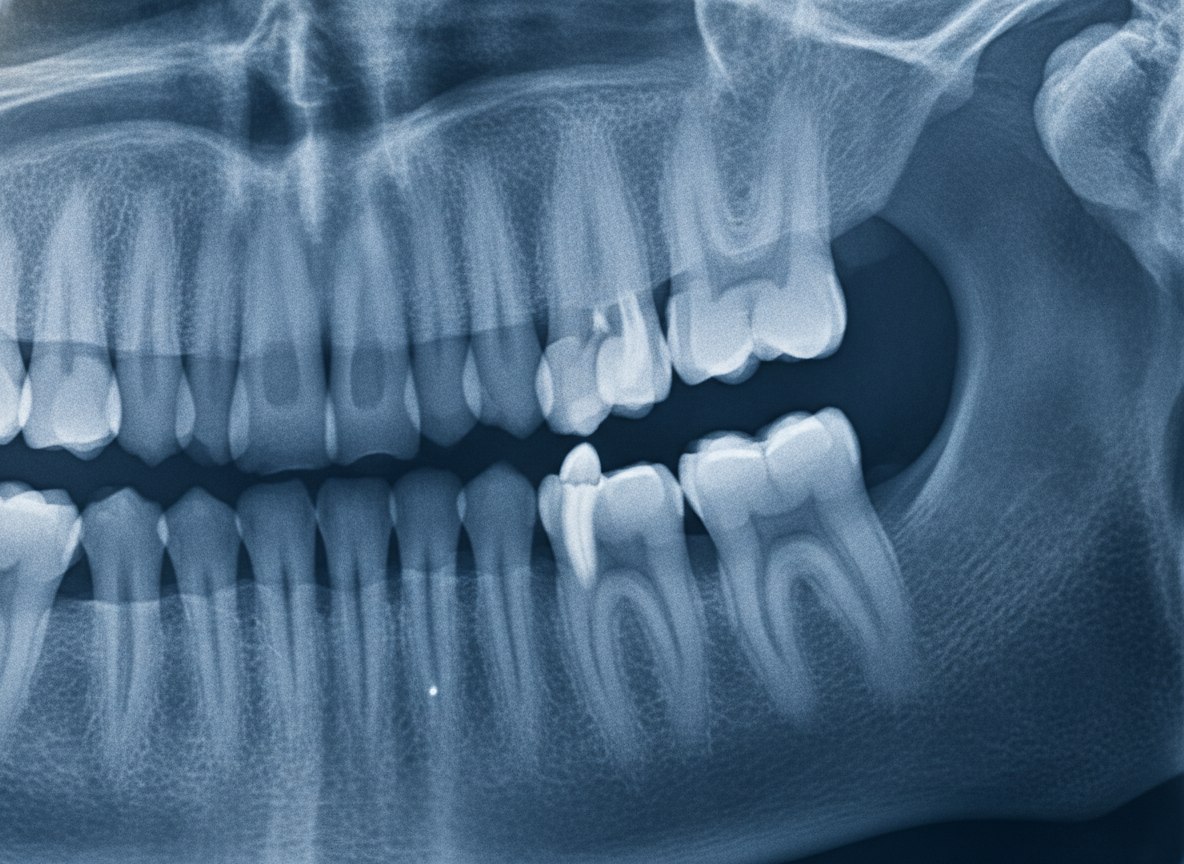

Оказалось, что под дёснами большинства людей дремлют зачатки дополнительных зубов. Третьего поколения. Они формируются у человека ещё на этапе внутриутробного развития, но их рост подавляется специальным белком USAG-1 — из-за чего эти структуры так и остаются в «спящем» состоянии.

Первая фаза клинических испытаний стартовала осенью 2024 года в больнице Киотского университета. В исследовании участвуют 30 здоровых мужчин от 30 до 64 лет — у каждого не хватает хотя бы одного коренного зуба.